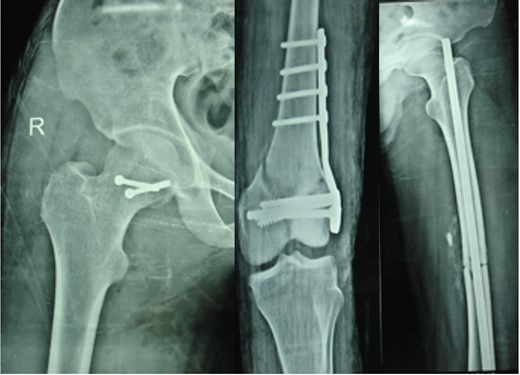

The right hip joint was approached via the Kocher-Langenbeck approach, fracture site was exposed with removal of fibrous tissue and the fracture involved mostly the infrafoveal non-weight bearing surface of the femoral head (Fig. 4). Following reduction of fracture, femoral head was fixed with two 4 mm cannulated cancellous screws that were introduced over a guide wire from the non-articular part under C-arm guidance (Fig. 5). Open reduction and plating was performed for the ipsilateral femoral condylar fracture. Closed reduction and intramedullary nailing of left femur was performed in the same sitting. The immediate postoperative X-ray was satisfactory (Fig. 6). The postoperative period was uneventful.

At 1- and 7-year follow-up, X-rays were satisfactory with no signs of osteonecrosis of femoral head (Figs 7 and 8). Nail from the left femur and right distal femoral plate were removed at the end of 2 years. The patient at 7 years post-surgery had a good functional assessment (Friedman and Wyman) score with X-ray bearing no signs of avascular necrosis or heterotrophic ossification, and the fracture had united. Over 7 years, patient who is a student by profession is bearing full weight and is successfully performing his personal and social duties. The active range of motion at right hip was 0–110° flexion and 0–10° extension, external rotation 0–30° with internal rotation 0–10° with slight loss of terminal abduction (Figs 9 and 10).